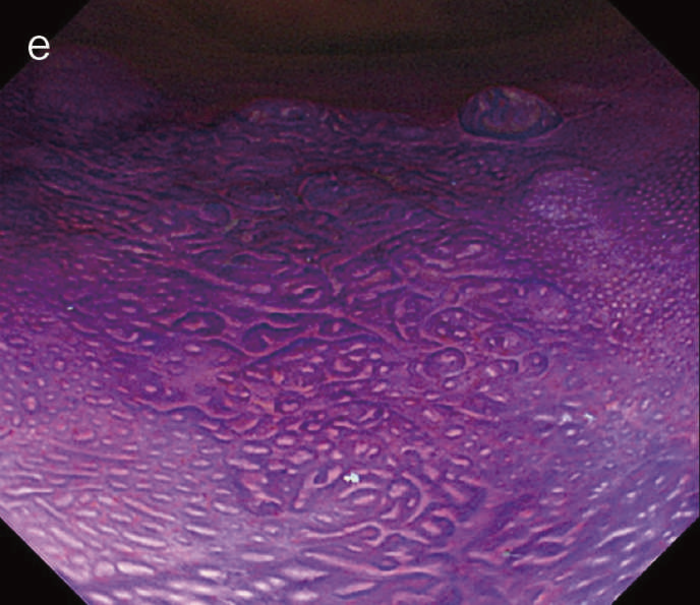

2)病理診断

- UC関連進行大腸癌の肉眼像は潰瘍浸潤型(3型),びまん浸潤型(4型)や分類不能型(5型)が多い。同初期病変の多くは隆起型,平坦型,あるいはその混合型であり,平坦型成分はdysplasiaの特徴といえる。

- 肉眼的特徴

通常の散発性進行大腸癌の多くは潰瘍限局型(2型)であるが,UC関連進行大腸癌は潰瘍浸潤型(3型),びまん浸潤型(4型)や分類不能型(5型)が多いとされる(図7)。初期病変であるdysplasiaの肉眼形態に関しては,混合型を含む約70%の症例が何らかの隆起成分を有することが報告されている1,2)。ただ同じ隆起といっても,UC関連大腸腫瘍の多くは境界不明瞭な丈の低い顆粒状・結節状・不整扁平隆起を呈する一方で,散発性腫瘍は有茎性もしくは亜有茎性病変,境界や立ち上がりが明瞭な病変であることが多く,詳細な肉眼形態の観察は両者の鑑別に重要である。二番目に多い肉眼形態は平坦型であり,全体の約30%を占める1,2)。散発性大腸腫瘍の平坦型は極めて頻度が低いことから,平坦型成分の存在もdysplasiaの特徴といえる(図8)。

図8 Dysplasiaの代表的な肉眼像(平坦型)

- 直腸部の赤色点線部より肛門側(左側)に拡がるdysplasia(平坦型)を認める。

- 同平坦部では組織学的に高分化管状腺癌(粘膜内癌)を認めた。

- 組織学的特徴

dysplasiaはその異型度によりLGDとHGDに二分される(図9)。LGDは基本的に核の極性が比較的保たれており,表層への分化傾向がみられることを特徴とし,しばしば反応性異型との鑑別を要する。多彩な形態像を示すこともdysplasiaの特徴である。味岡らは,UC関連大腸腫瘍を5つの特殊なパターン(表層分化を示す分化型腺癌,分化細胞を豊富にもつ分化型腺癌,分化細胞に乏しい分化型腺癌,未分化型腺癌または分化型腺癌の脱分化,癌の判定が困難な分化型腫瘍)に分類し報告している3)。2019年に出版されたWHO分類には,IBDを背景に発生する粘膜内腫瘍をInflammatory bowel disease-associated dysplasia of the colorectumと呼称し,組織形態に基づき,intestinal(adenomatous)subtype,serrated subtype,mucinous type,a subtype with eosinophilic cytoplasm and marked goblet cell depletion,crypt cell subtypeやこれらの組織像が混在したmixed subtypeなどが存在すると記載されている4)(図10)。

このように多彩な像を呈するdysplasiaでは,特に異型度が低い場合に反応性異型との鑑別にしばしば難渋するが,dystrophic goblet cell,endocrine cell hyperplasia,Paneth細胞化生などの特徴的な上皮細胞分化異常を示す特殊な異型上皮の存在が形態学的な鑑別として有用である。また,dysplasiaでは,腫瘍発生早期の段階よりTP53遺伝子異常が起こることが知られている。したがって,上記の形態学的な異常とともに,免疫染色におけるp53蛋白異常発現の有無が反応性異型や散発性腺腫との鑑別において重要となる(TP53遺伝子変異が見られる際には,免疫染色においてp53蛋白過剰発現あるいは完全欠失を示すことが知られている)。これまでに,一般大腸腺腫・癌ではp53蛋白過剰発現はその異型度に相関するのに対し(腺腫で0.8~3.4%,低異型度癌で35.3%,高異型度癌で71.7%),dysplasiaでは低異型度の段階から高頻度(75%)にp53蛋白過剰発現を呈することが報告されている5)。したがって,特に低異型度腫瘍でp53蛋白異常発現パターンを示す場合はdysplasiaの可能性が高く,反応性異型との鑑別において診断的意義が高い。また,表層分化傾向を示すLGDではp53蛋白の過剰発現がある場合でも表層部ではp53蛋白の発現減弱がしばしば観察されるのに対し(unique basal patternと呼ばれる),HGDでは全層性にp53蛋白過剰発現を示すことが多い。Ki-67(増殖マーカー)染色では,dysplasiaでは細胞増殖帯が粘膜深層~中層に位置するが(bottom-up pattern),散発性腺腫では細胞増殖帯が腺管表層~中層に分布することが知られている(top-down pattern)。これらの免疫染色パターンは,dysplasiaと反応性異型や散発性腺腫との鑑別の際に重要な手がかりとなる(図9,図11)(CQ 12,CQ 13)。